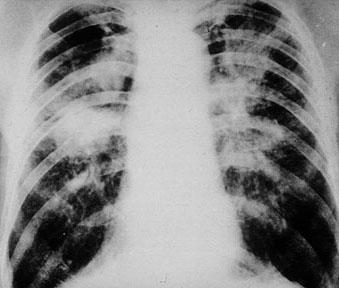

Бели дробове с характерен мозаечен вид. Под висцералната плевра прозира сив до черен на цвят пигмент – въглищен прах,натрупан под формата на ивици и петна. По същият начин са променени и перибронхиалните лимфни възли, видими в областта на белодробните хилуси